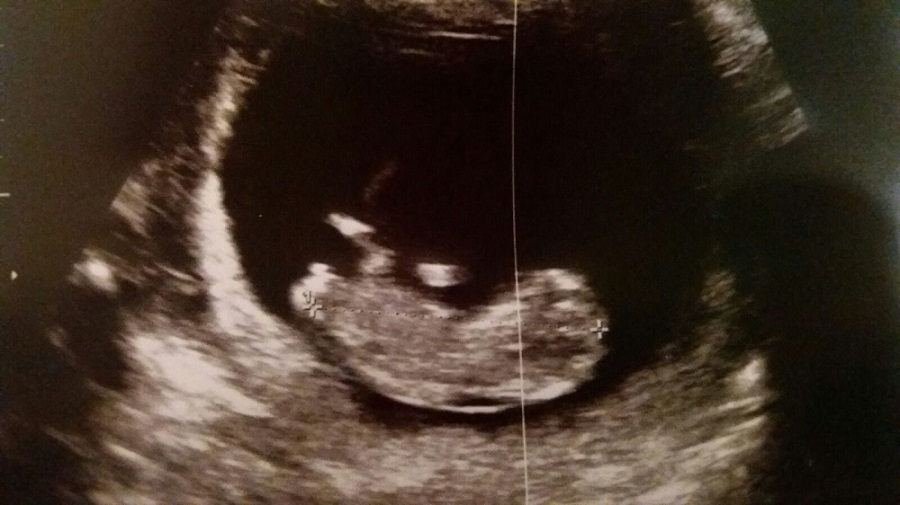

Hi! 11 weeks scan...can anybody help me telling if boy or girl?? thanks!!Attachment 33268

I would have guessed a boy from this picture, but I've since learned that 11 weeks is too early to tell x

11 weeks is too early as most look girly at that stage. 13 weeks is the best time or at least after 12.